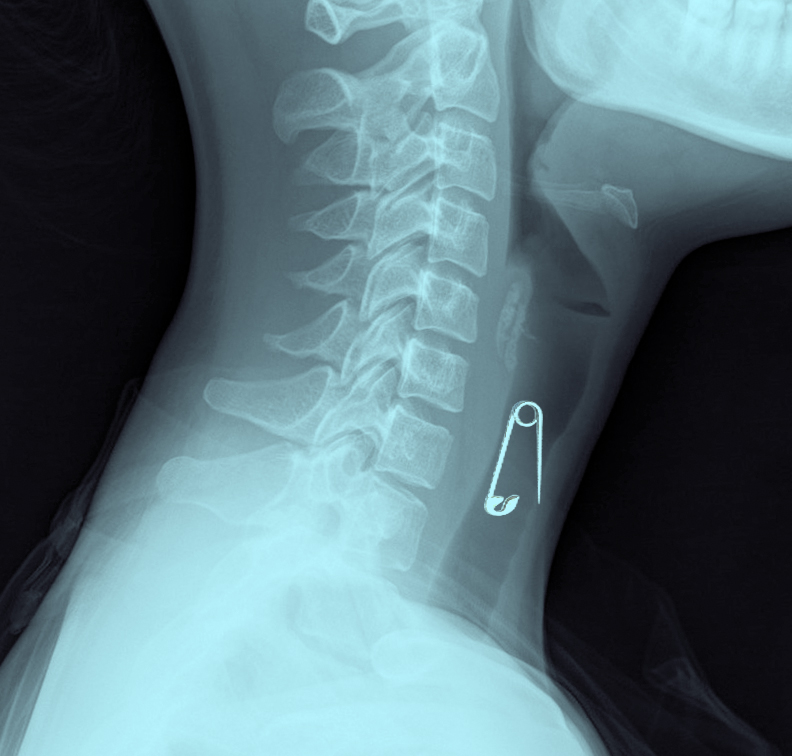

শফিকুল ইসলাম জানান, বুধবার (২৪ আগস্ট) দিবাগত রাত ১২টার দিকে জিদনি খাবে না বলে বায়না ধরে। একপর্যায়ে শিশুটিকে মেঝেতে নামিয়ে খেলার ছলে নুডুলস খাওয়ায়। এর কিছুক্ষণের মধ্যে জিদনি বমি করতে শুরু করে এবং অসুস্থ হয়ে পড়লে তাকে বাঘা সেবা ক্লিনিকে ভর্তি করানো হয়। সেখানকার চিকিৎসকরা রাতেই তাকে রাজশাহী মেডিকেল কলেজ হাসপাতালে প্রেরণ করে। রাজশাহী মেডিকেল কলেজে ভর্তির পর এক্সরে করানো হয়। দেখা যায়, গলায় আটকে আছে আস্ত সেফটিপিন। দায়িত্বরত চিকিৎসক জানিয়েছেন, রাজশাহী মেডিকেল কলেজ হাসপাতালে গলার ভেতর খেকে সেফটিপিন বের করার মতো চিকিৎসা সরঞ্জাম নেই। সে কারণে ঢাকা মেডিকেল কলেজ হাসপাতালে রেফার্ড করা হয়েছে। শুক্রবার দুপুরে পরিবারের লোকজন জিদনিকে নিয়ে ঢাকায় রওয়ানা হয়েছেন।